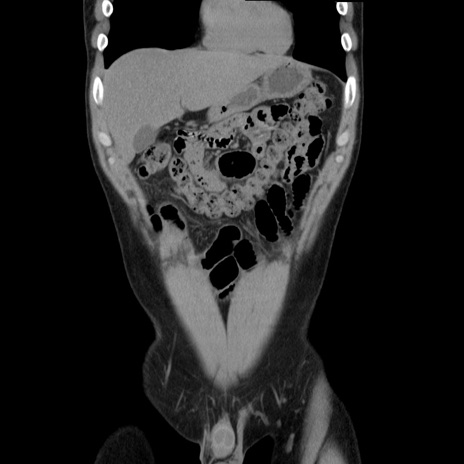

症例36(冠状断像)

【症例】20歳代 男性

【主訴】心窩部痛

【現病歴】今朝より上腹部痛あり。一旦軽快していたが再度出現したため救急要請。昨日夕に白身の魚を含む刺身を食べた。

【身体所見】BP 136/89mmHg、HR 74/min、BT 37.0℃、腹部:膨満、軟、心窩部に圧痛あり。反跳痛なし、筋性防御なし、腸雑音やや亢進あり。

【データ】WBC 17700、CRP 0.48